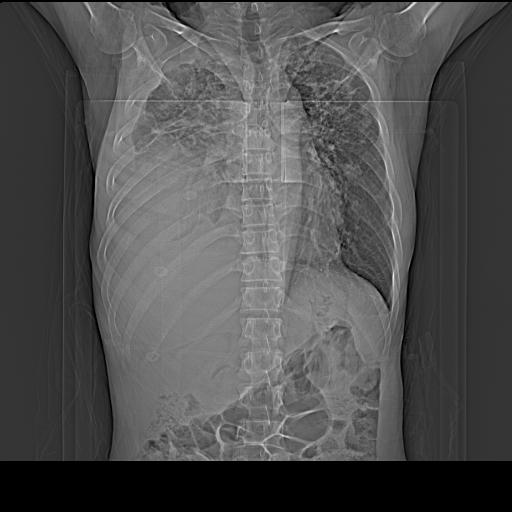

男性,44岁,结核病史多年。现胸闷气短,咳嗽,偶咳血。

右侧胸腔积液

右肺下叶不张

双肺多发结节影最分空洞形成考虑占位不除外结核

双肺陈旧性病变

1、右侧大量胸腔积液伴右肺压缩性膨胀不全,建议抽液治疗后复查 2、两肺继发性tb伴空洞形成。

1)两肺继发性肺结核伴空洞形成,左肺多发性结核球。2)右侧大量胸腔积液伴右肺部分膨胀不全。3)纵隔淋巴结肿大。

吉大一院胸水抽检结果:结核性胸水